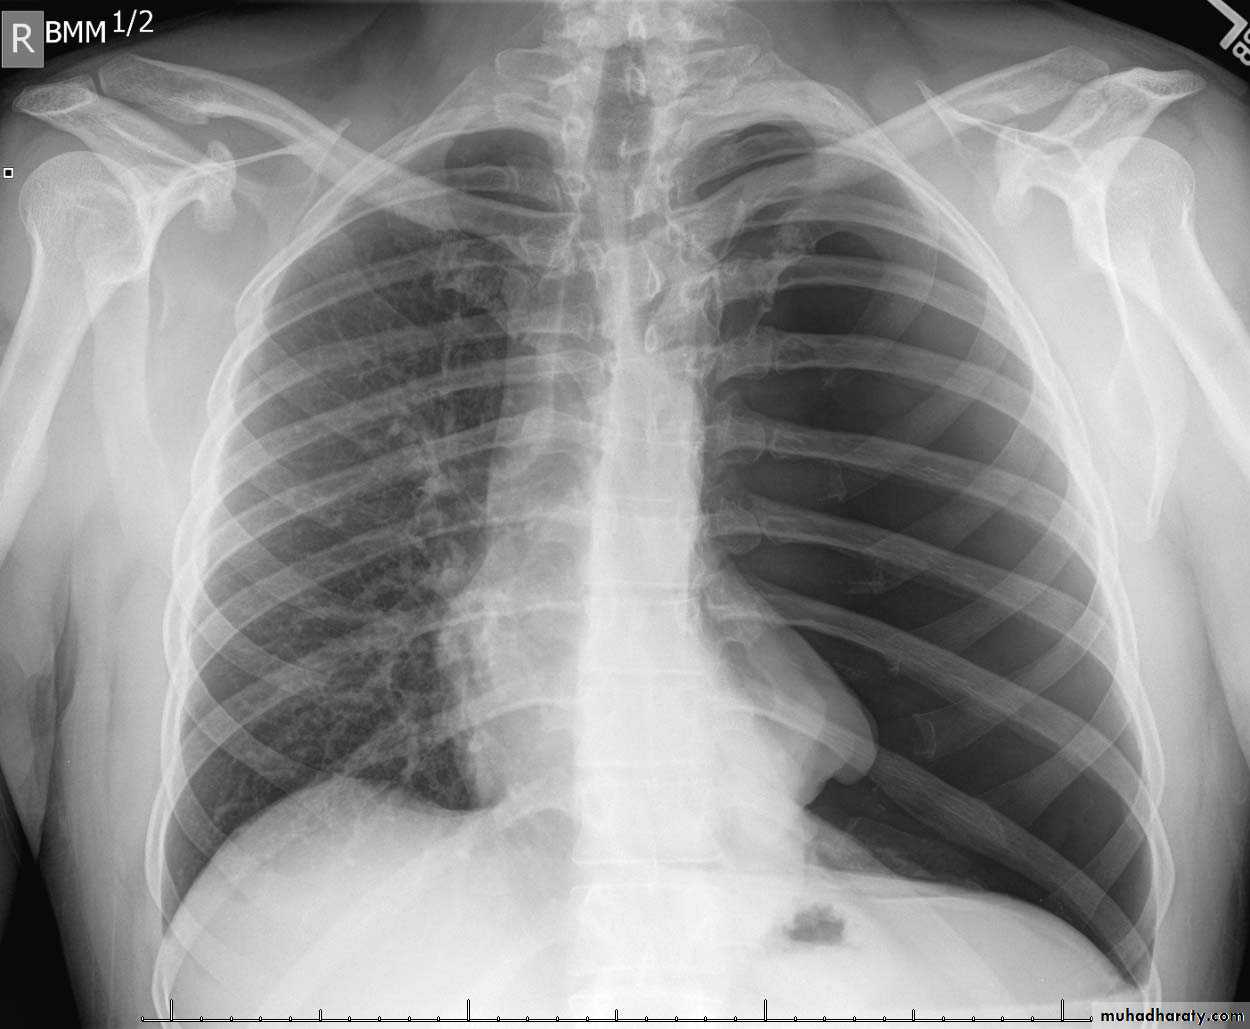

Pleural effusion

Pleural effusion tends to be used as a catch-all term denoting a collection of fluid within the pleural space. This can be further divided into exudates and transudates depending on the biochemical analysis of aspirated pleural fluid. Essentially it represents any pathological process which overwhelms the pleura's ability to reabsorb fluid.Radiographic appearances

Plain radiographChest radiographs are the most commonly used examination to assess for presence of a pleural effusion, however it should be noted that on a routine erect chest x-ray as much as 250-600 ml of fluid is required before it becomes evident 6. A lateral decubitus film is most sensitive, able to identify even a small amount of fluid. At the other extreme, supine films can mask large quantities of fluid.

CXR (erect)

Both PA and AP erect films are insensitive to small amounts of fluid. Features include:

blunting of the costophrenic angle

blunting of the cardiophrenic angle

fluid within the horizontal or oblique fissures

eventually a meniscus will be seen, on frontal films seen laterally and gently sloping medially (note: